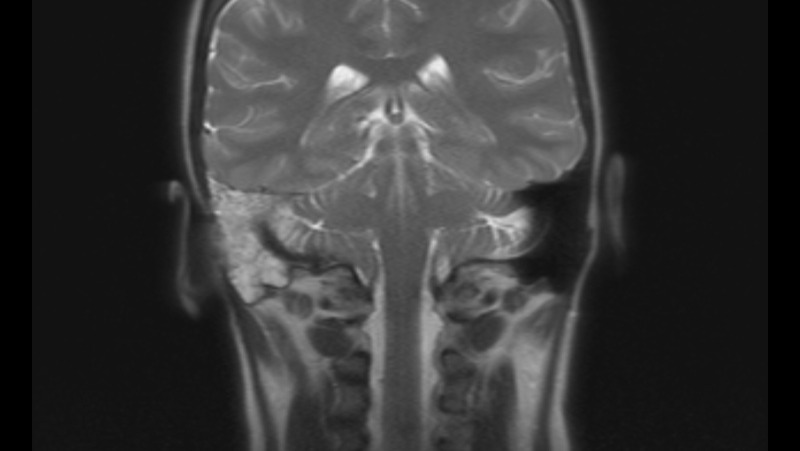

On May 25, 2022, after experiencing debilitating symptoms, I was diagnosed with an Acoustic Neuroma brain tumor.

The tumor had enveloped my auditory nerve and while small was also causing significant damage to my facial and vestibular nerves.

A retrosigmoid craniotomy to remove the tumor was performed on August 12, 2022 at Mayo Clinic in Rochester, Minnesota. This is highly invasive surgery, requiring the retraction of the cerebellum for several hours and highly skilled neurosurgeons.

Two days after my brain surgery I developed a life threatening cerebrospinal fluid leak. I endured a spinal tap without localized pain meds, repeated lumbar drains, then another cranial surgery to repair the leak. This repair involved temporarily cutting off my right ear and placing a fat graft within my skull.

Since these surgeries I have endured chronic cranial pain at levels of 4 to 6 out of 10. Depending on circumstances the pain rises to 8 or 9 out of 10 regularly. I have barely slept since the surgeries as I must take medication every 6 hours around the clock just to maintain my "normal" pain level. Because of the damage to my vestibular nerve, I needed a cane to walk until March of 2023. Because of the need to remove my auditory nerve along with the tumor, I am now permanently deaf on my right side. I also have constant roaring tinnitus, and a significant build up of unresolved fluid.

I will need a yearly brain mri to monitor for tumor regrowth. My neurologist has recently prescribed physical therapy to begin late November 2023. He believes the severing of a major nerve in my neck is responsible for the majority of the chronic pain, and that massage may relieve it to a degree without the need for additional medication.